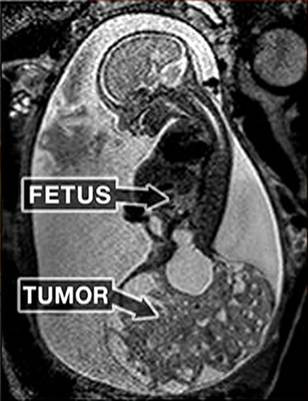

Một trường hợp được sinh ra hai lần khác là bé Macie Hope. Lần “chào đời” đầu tiên là khi bé Macie mới được 6 tháng trong bụng mẹ lúc này mới nặng hơn 100g. Khi siêu âm bác sĩ phát hiện ra một khối u ở phần xương cụt to không kém thì thai nhi và cũng chứa đầy các mạch máu. Tuy không phải là ung thư nhưng cũng có thể ảnh hưởng đến tính mạng của thai nhi nếu không được cắt bỏ kịp thời. (Ảnh: Today)

Bác sĩ đã tiến hành phẫu thuật mổ lấy thai nhi ra khỏi tử cung để cắt bỏ khối u trong lúc phần đầu và thân trên vẫn nằm nguyên trong bụng. Ca mổ diễn ra nhanh chóng trong 20 phút. Thai nhi sau đó may mắn phát triển bình thường trong bụng mẹ và chào đời một cách kỳ diệu. (Ảnh: Wereblog)